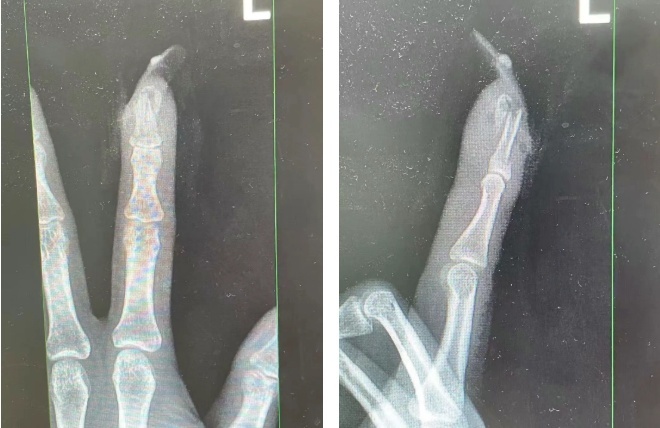

▲王女士受伤手指的X光影像。来源:杭州市临平区中西医结合医院

经检查

王女士指甲断裂,部分甲床外露

医生表示如果没有美甲

伤害不会这么严重